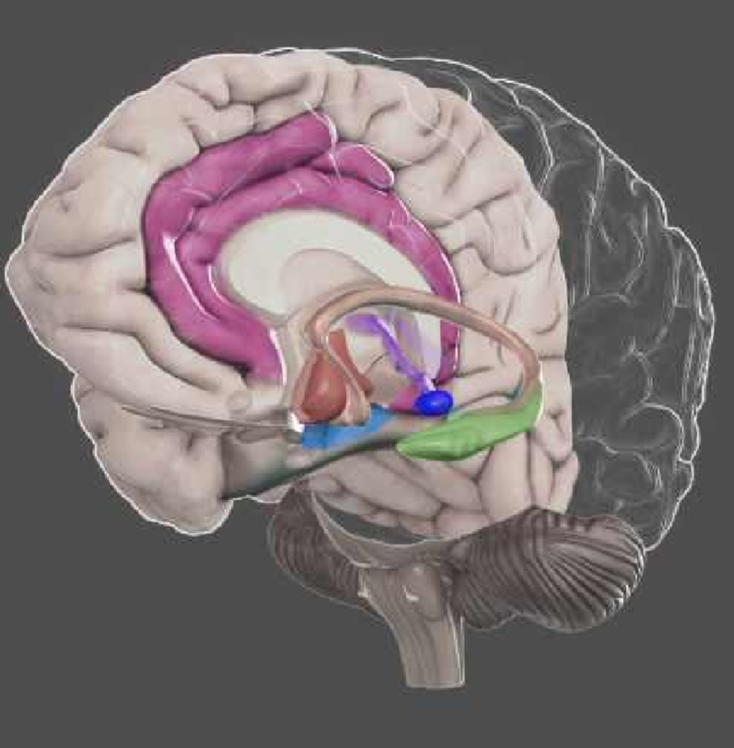

Con la técnica se estimula, en concreto, la corteza prefrontal dorsolateral como tratamiento contra los síntomas de la depresión.

Estos resultados fueron asociados a una disminución en la conectividad entre la corteza cingulada anterior subgenual y las áreas relacionadas a la red del modo por defecto, al igual que entre la corteza prefrontal dorsolateral y la ínsula.

Por otro lado, Terraneo et al. (2015), condujeron un experimento clínico con TMS en consumidores de cocaína. En el experimento se analizaba si la activación con TMS de la corteza prefrontal dorsolateral reducía el consumo.